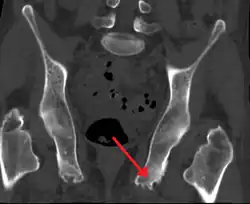

Em medicina, uma entesopatia se refere a um distúrbio da êntese (anexos ósseos).[1] Exemplos incluem espondiloartropatias como a espondilite anquilosante, a fascite plantar e a tendinite do calcâneo.